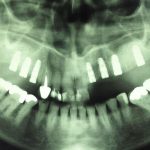

جراحی گذاشتن ایمپلنت های دندانی جهت جایگزینی دندانهای از دست رفته

گذاشتن ايمپلنت همزمان با كشيدن دندان

جراحی پیوند استخوان جهت افزایش میزان استخوان و آماده سازی برای گذاشتن ایمپنت

جراحی سینوس لیفت بصورت باز و بسته برای گذاشتن ایمپلنت

ایمپلنت چیست؟

ایمپلنت مجموع قطعاتی است که با جراحی داخل فک ثابت میشوند روی آن دندان مصنوعی قرار میگیرد و در نهایت ظاهری مشابه با دندان طبیعی پیدا میکند.

بهطور کلی برای گذاشتن ایمپلنت دندان چندین مرحله باید انجام شود تا قطعات تشکیل دهنده در کنار یکدیگر قرار گیرند و بیمار بتواند به جای دندان طبیعی از آن استفاده کند. ایمپلنت از نظر ظاهری مشابه دندان طبیعی است و در دهان همان حس طبیعی را برای جویدن القا میکند و سوء هاضمه ایجاد شده بر اثر ناتوانی در جویدن غذا را برطرف مینماید.

ایمپلنت دندان برای جایگزین کردن یک یا چندین دندان از دست رفته کاربرد دارد و میتواند برای تمام دندانها به صورت ثابت یا متحرک استفاده شود. در هر دو حالت فوق کلمه ایمپلنت استفاده میشود اما حالت دوم بیانگر معنی واقعی ایمپلنت است و به مجموعهای از قطعات ایمپلنت گفته میشود و هر کدام از قطعات به تنهایی نام و کارایی مجزایی دارند.